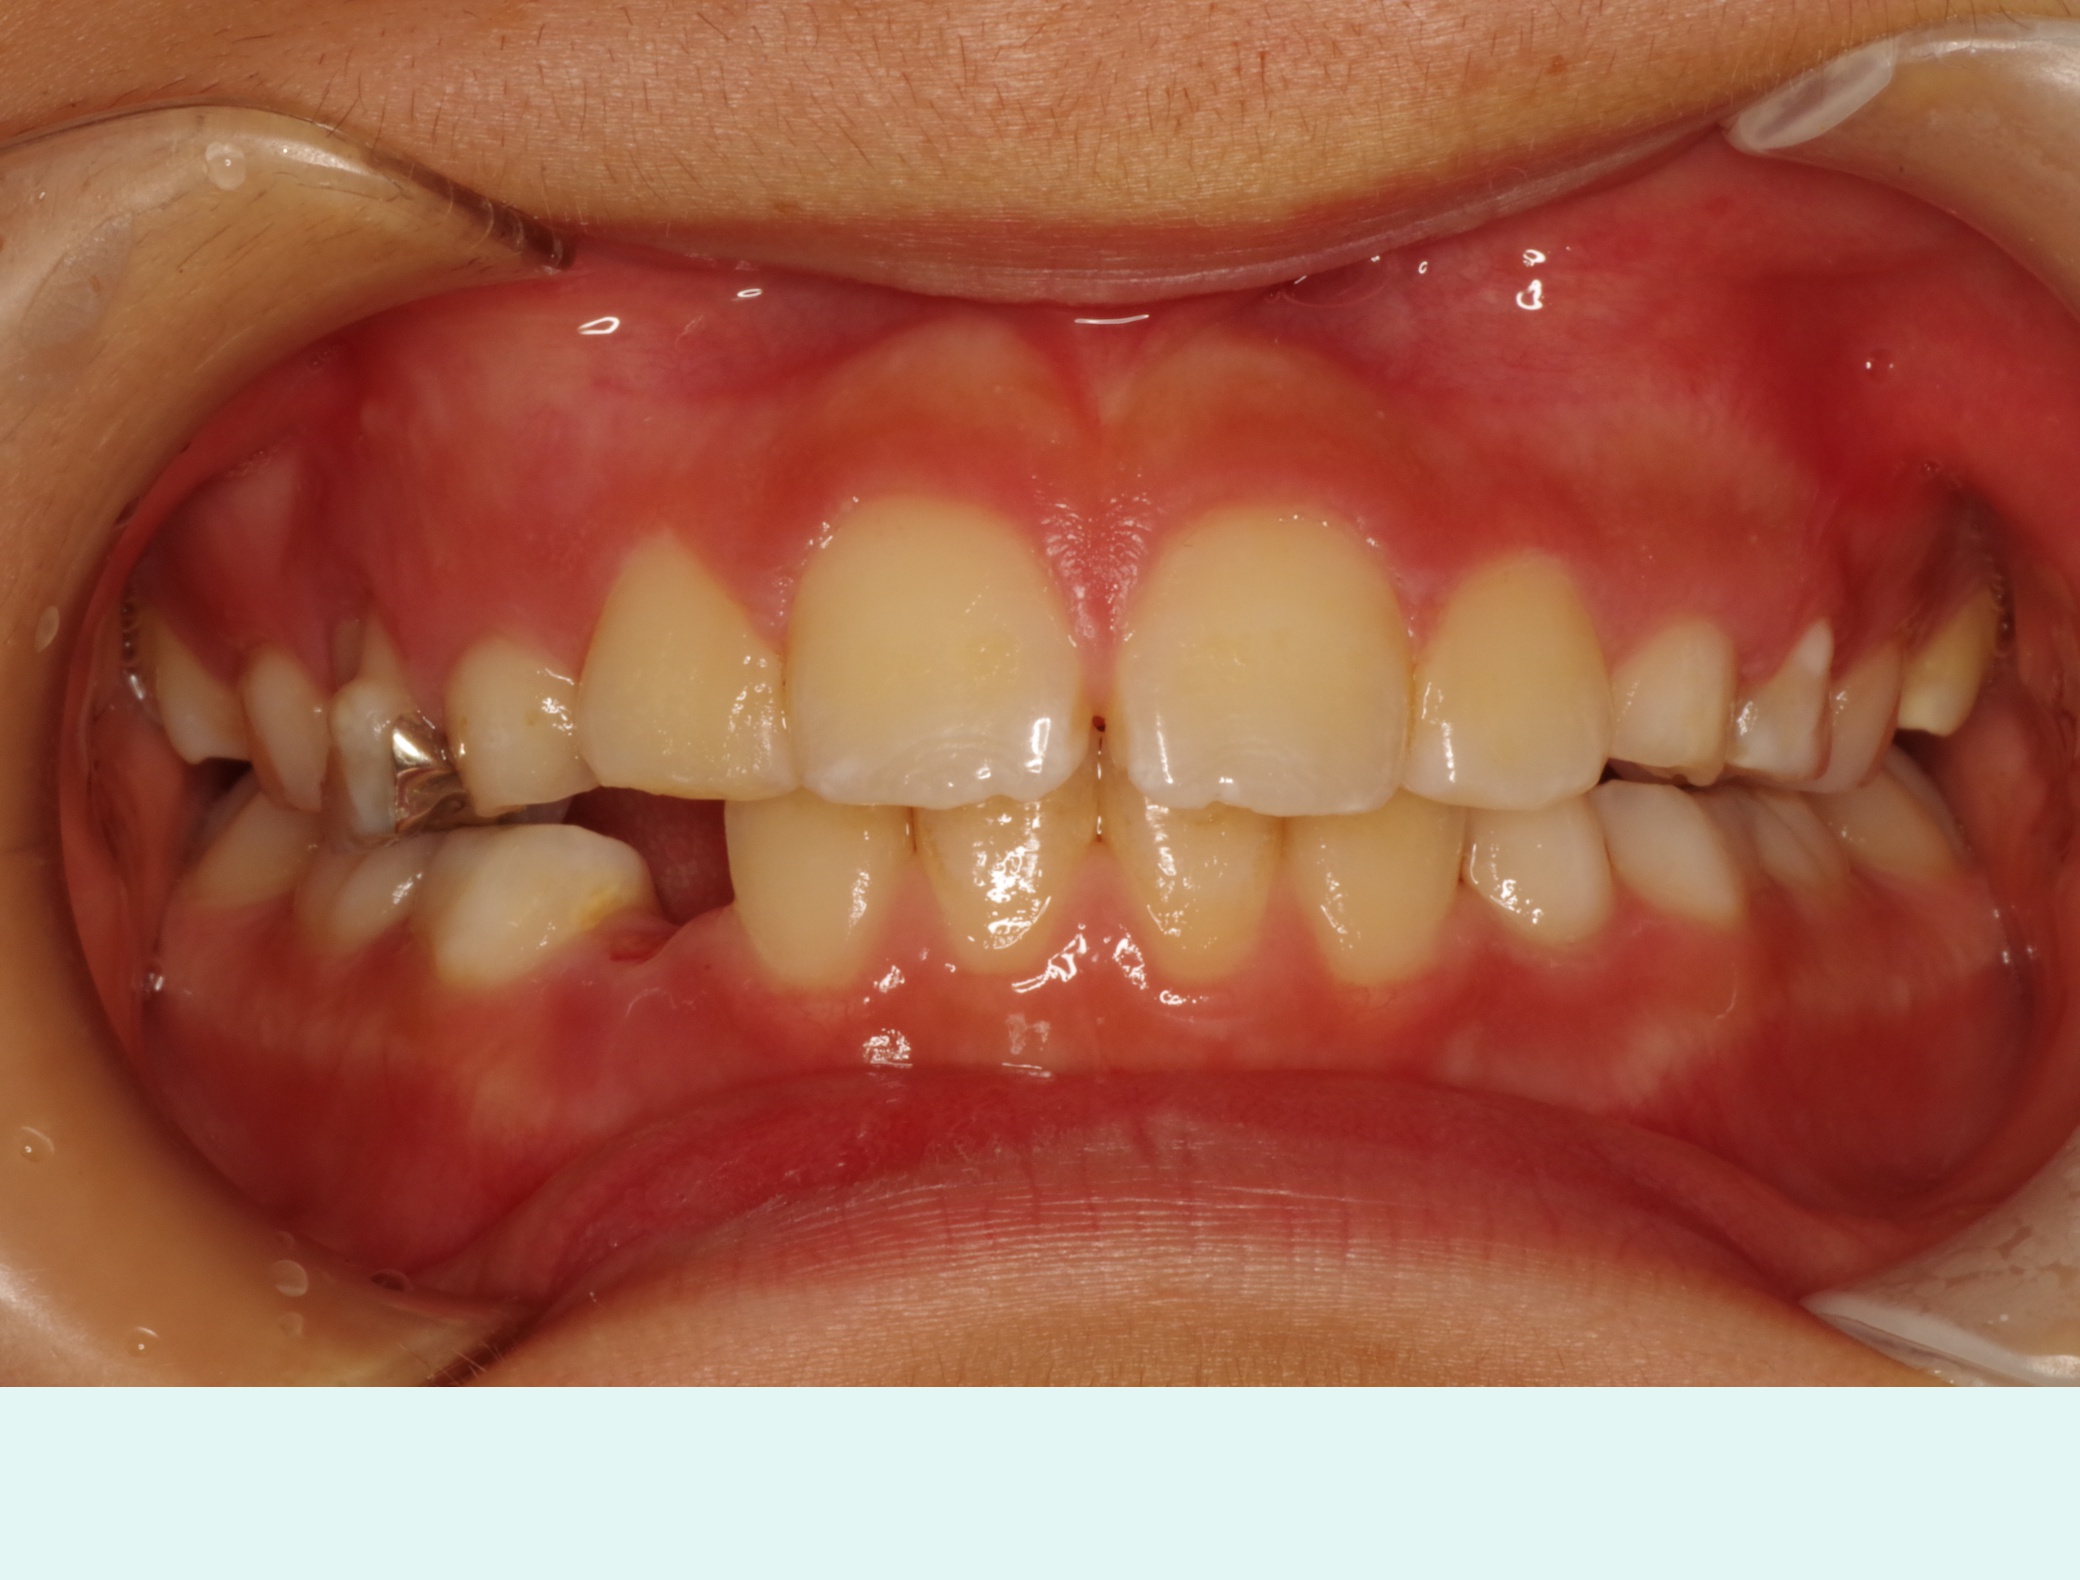

当医院ではお子様の矯正に顎の成長をサポートするような装置を使い、歯ならびを矯正します。

取り外し出来る装置のため、お子様の負担も少なく、気軽に使用できます。

当医院では歯並びだけでなく咬み合わせの確認も行っていきます。

適応年齢は小学生~中学生ですが、それ以前の年齢のお子様も定期健診で様子を診ていきますのでお気軽にご相談下さい。